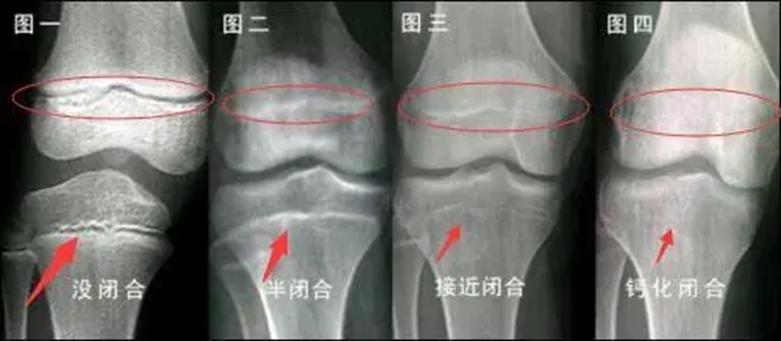

骨骺线闭合过程示意图 来源 | 百度百科

人全身的发育状况可以从骨骼发育中窥见一斑,骨骼的发育又与骨骺的形态有着密切的联系。骨骺有四个生长阶段: 生发期、增殖期、塑形期以及闭合期 ,骨骺的发育受到很多因素的影响,但是生长阶段不会因为骨的发育而有所提前。所以可以 从骨骺的生长时期情况判断骨是否还在生长。

人体骨骼在发育的过程中,骨头两端的软骨中出现的骨化点称为 骨骺 。在人体骨骼还未成熟时,一些骨骼还呈现软骨的状态。当身体发育完成,这一部分软骨就会完全骨化,变成一条紧密的缝。 一般在16至20岁之间人体会完全长成,骨骺线闭合,身高固定下来,当然也会因为个体的差异而有所不同。